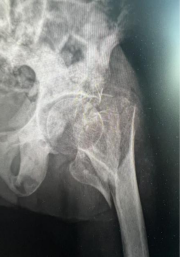

患者因意外跌倒导致髋部骨折(医学上称为“人生最后一次骨折”),同时伴有高血压、糖尿病及心肺功能减退等基础疾病。面对超高龄、高风险的双重挑战,响水县人民医院骨科团队迅速启动多学科协作(MDT)机制,联合麻醉科、心血管内科、重症医学科等专家进行综合评估。

微创技术应用:采用闭合复位髓内钉固定术,减少软组织损伤,手术时间控制在1小时内。

医院数据显示,近五年来80岁以上髋部骨折患者实施手术221余例,90-99岁髋部骨折患者实施手术71例。100岁以上髋部骨折患者实施手术4例。